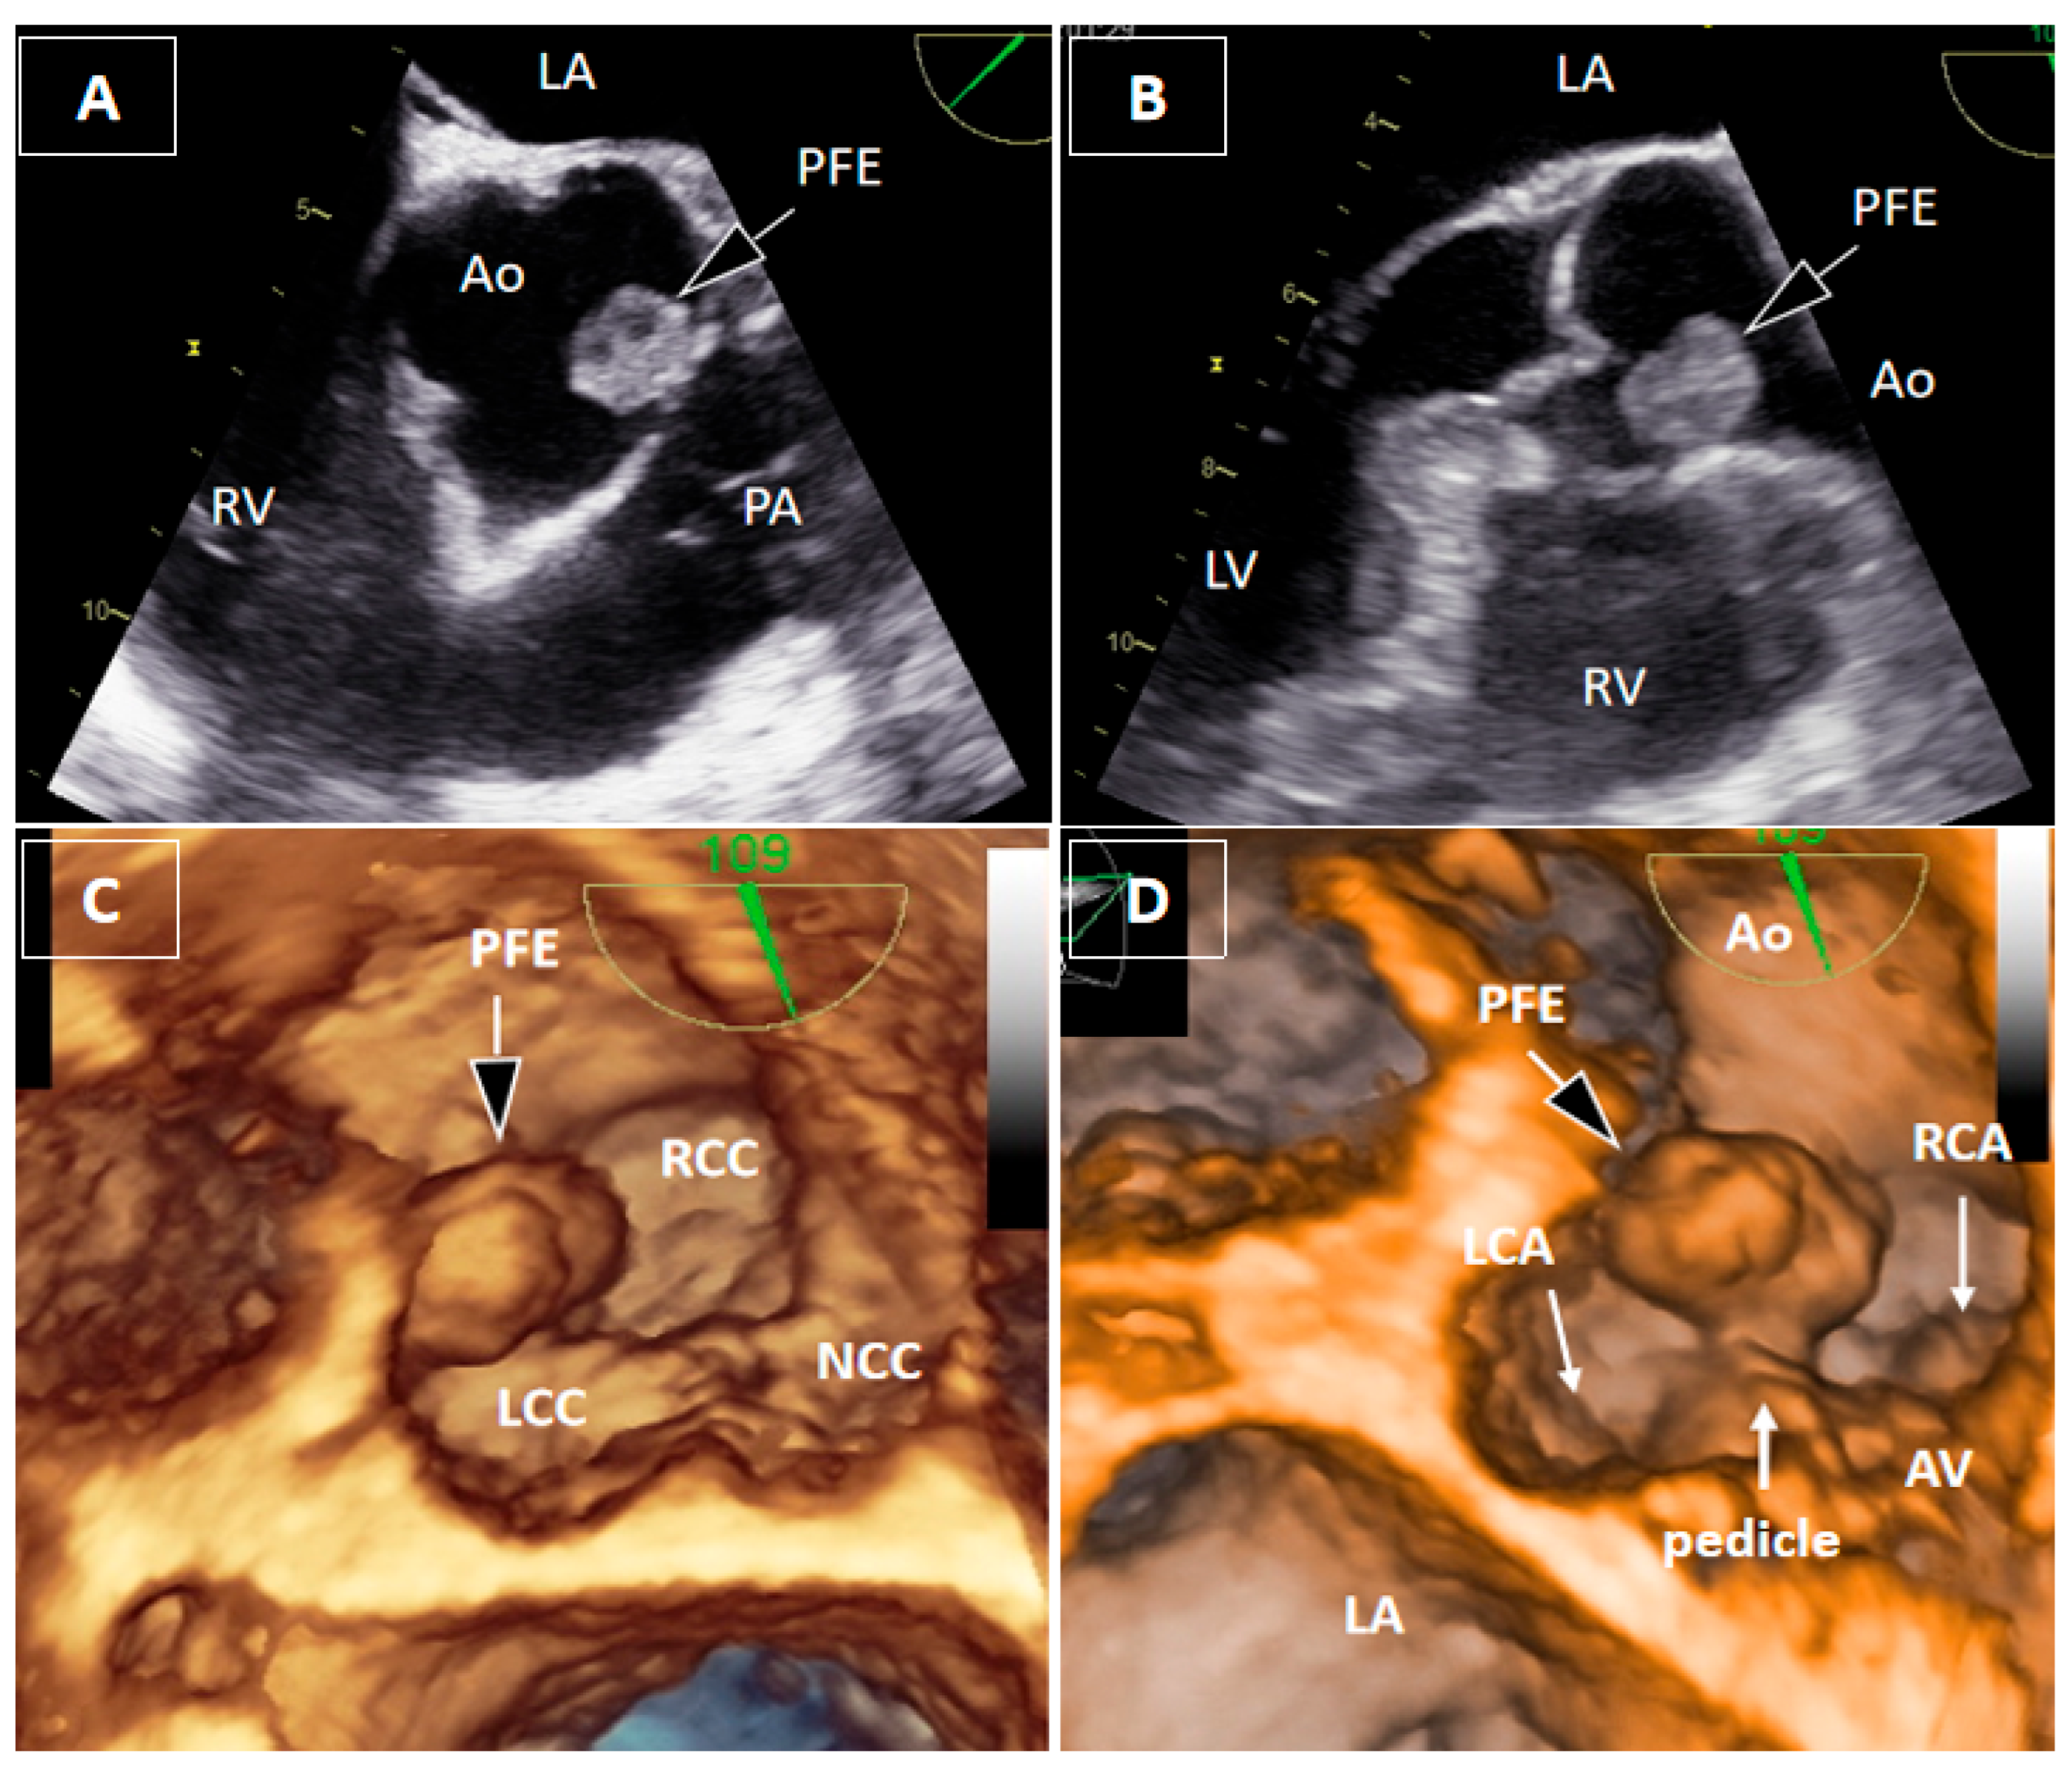

Papillary Fibroelastoma of the Aortic Root Causing Intermittent Coronary Ostial Obstruction: The Diagnostic Power of 3D Transesophageal Echocardiography

Bečić, T.; Perković-Avelini, R.; Fabijanić, D. Papillary Fibroelastoma of the Aortic Root Causing Intermittent Coronary Ostial Obstruction: The Diagnostic Power of 3D Transesophageal Echocardiography. Diagnostics 2026, 16, 168. https://doi.org/10.3390/diagnostics16010168